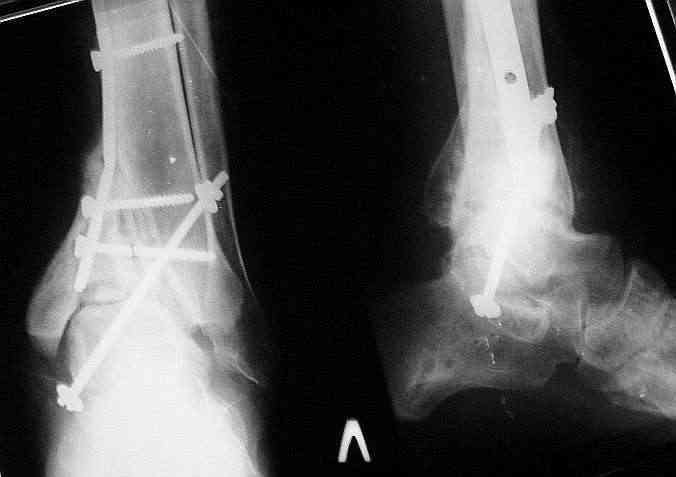

Было решено, уже по ходу операции, выполнить артродез болтом-стяжкой, тем самым компрессируя резецированные суставные поверхности и смещая стопу латерально, дабы нивелировать варусную деформацию и восстанавливая тем самым опорную ось всей конечности.

Вчера (прошло около 8 месяцев)больной обратился ко мне в очередной раз с жалобами на боли умеренно-жгучего характера в области выстояния концов болта-стяжки. На момент осмотра:укорочение левой нижней конечности на 1,5 см; гипотрофия медиальной группы мышц голени и четырехглавой мышцы бедра; передвигается без дополнительной опоры в ортопедической обуви на растояние до 5 км; работает приемщиком цветных металлов (приходится перетаскивать грузы). Нарентгенограмме, насколько это можно видеть, костного блока сформировать не удалось, но движений в голеностопном суставе нет - ни активных, ни пассивных. Послеоперационные рубцы б/о; свищей и нагноения не было. Активно больногонаблюдать не приходилось, т.к. проживает в другом городе.

Стоит ли необходимость удаления болта-стяжки из-за болевого синдрома?

ЗЫ: Прошу прощения за очень низкое качество представленных ренгенограмм. Буду очень признателен за комментарии.